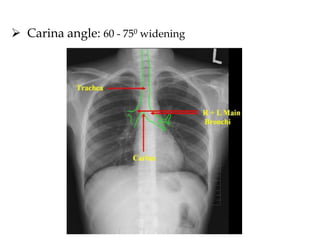

B. TRACHEA:

 Should be examined for:

• Narrowing

• Displacement

• Intraluminal lesions

 Position: Central, slightly deviated towards

Right around the aortic knuckle

 Calibre:

• Even

• Max. Coronal: 25mm (M), 21mm (F)

 Carina angle: 60 - 750 widening

 Carina angle:60 - 750 widening